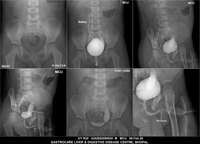

Section: URETHROGRAM

Total: 95 Cases